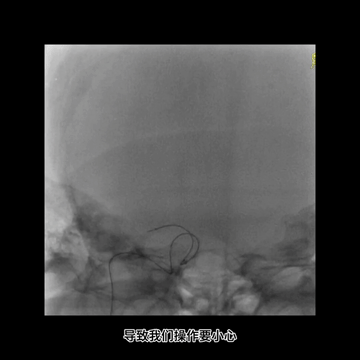

中间管内衬.018"导丝(Command 18),并尽力推高长鞘,在增强支撑下把中间管头端推送至颈内动脉末端,以增加对微导管微导丝的支撑性。